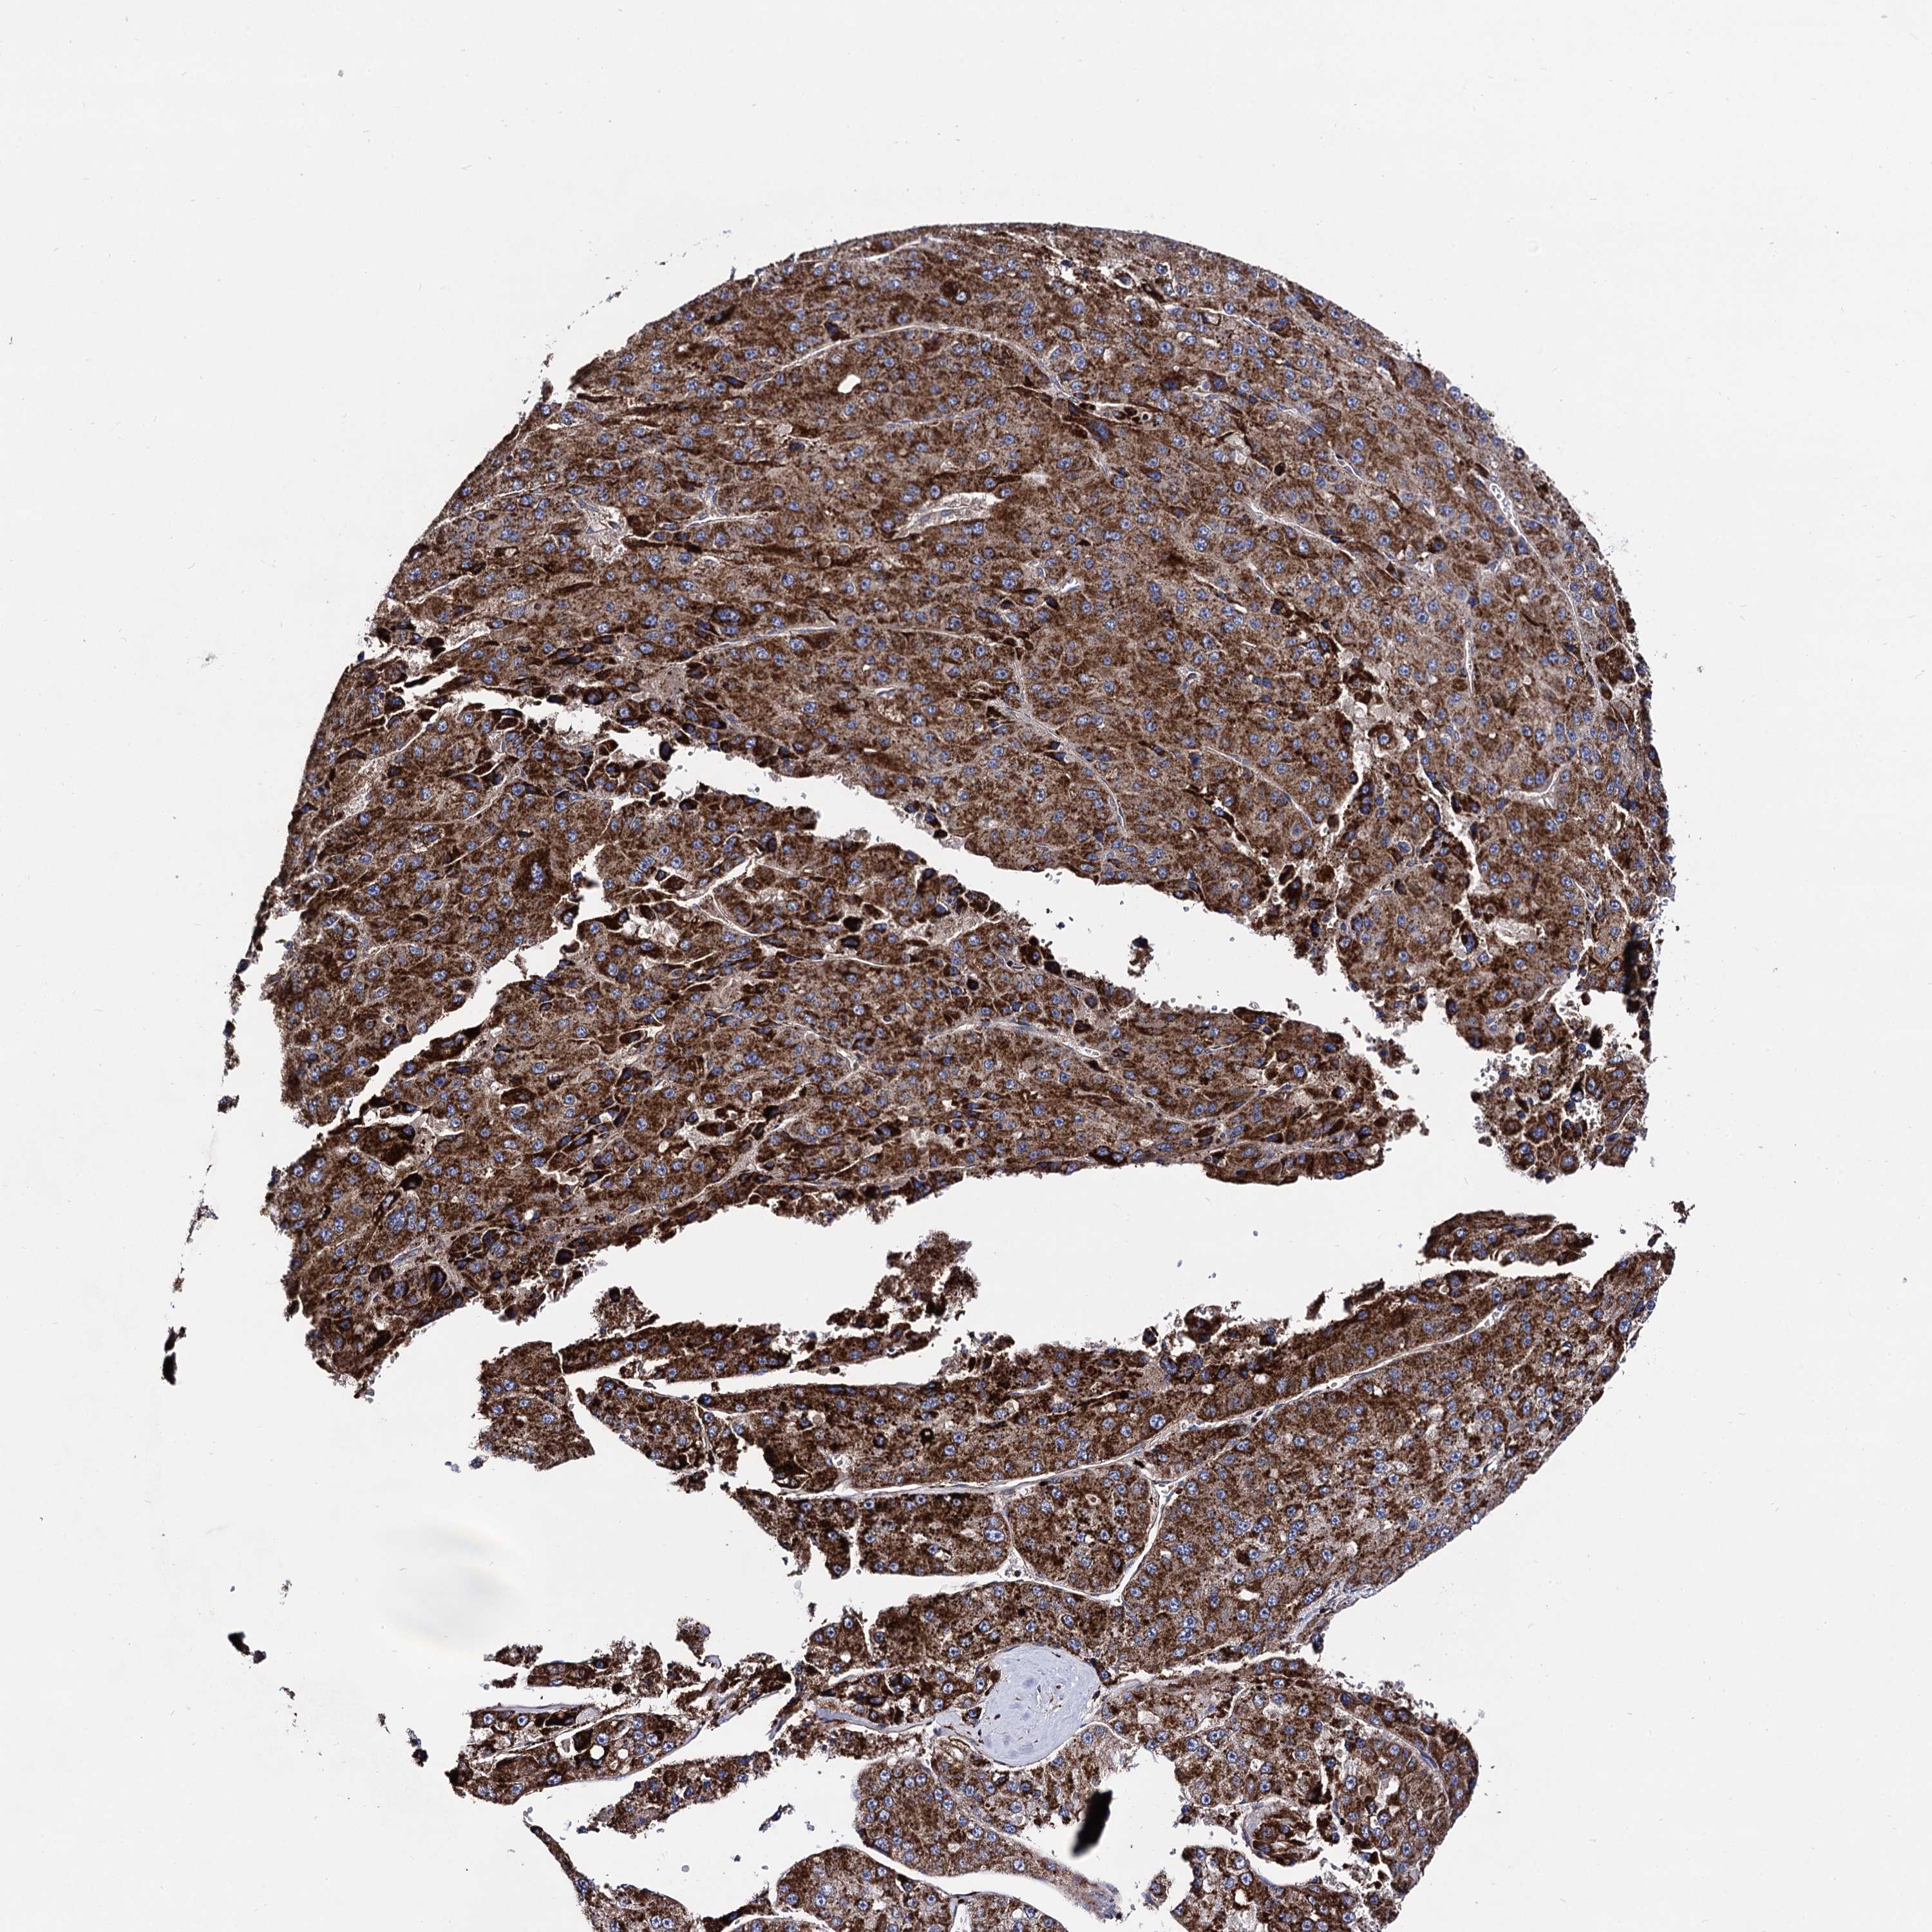

LIVER CANCER - Protein expressioni

A mouse-over function shows sample information and annotation data. Click on an image to view it in a full screen mode. Samples can be filtered based on level of antibody staining by selecting one or several of the following categories: high, medium, low and not detected. The assay and annotation is described here.

Note that samples used for immunohistochemistry by the Human Protein Atlas do not correspond to samples in the TCGA dataset.

Antibody stainingi

Antibody staining in the annotated cell types in the current human tissue is reported as not detected, low, medium, or high, based on conventional immunohistochemistry profiling in selected tissues. This score is based on the combination of the staining intensity and fraction of stained cells.

Each image is clickable and will lead to virtual microscopy that enables deeper exploration of all samples and also displays staining intensity scores, fraction scores and subcellular localization as well as patient and tissue information for each sample.

Antibody HPA040845

Staining

High

Medium

Low

Not detected

Intensity

Strong

Moderate

Weak

Negative

Quantity

>75%

75%-25%

<25%

None

Location

Nuclear

Cytoplasmic/membranous

Cytoplasmic/membranous,nuclear

Cholangiocarcinoma

Carcinoma, Hepatocellular, NOS